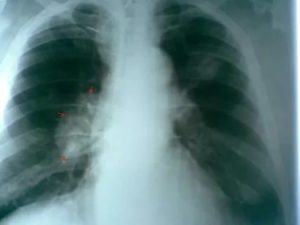

Вероятность того, что онкология на ранней стадии будет случайным образом обнаружена, остается крайне низкой. Во-первых, разрешение стандартных рентген установок не позволяет визуализировать затемнения диаметром меньше 5 мм. Во-вторых, только явные или дополнительные признаки рака легких дадут повод к углубленному и более внимательному изучению снимков.

Важно! Если отсутствуют первые симптомы злокачественных опухолей в органах грудной клетки, врач обнаруживает их только когда их диаметр превышает 5 мм.

В диагностической практике бывают случаи, когда не видны опухоли на рентгене. Это возможно в случае малого размера новообразования (меньше 5 мм в диаметре) или при наслоении теней ребер и других органов грудной клетки в проекции опухоли.

Онкологическая патология органов дыхания на рентгеновском снимке обозначается в виде небольшого затемнения. На острой стадии его выявить крайне трудно, поскольку сама патология имеет небольшой размер. Онкологические признаки можно заметить только если площадь поражения больше 2 мм в диаметре. Снимок рентгена покажет вторичные признаки образования онкологического очага.

Начальная стадия онкологического заболевания проходит без увеличения пораженной площади. Поэтому на рентгенографическом снимке первичная стадия не отображается или видна нечетко.

На такой стадии размер и форма карциномы составляет от 2 мм и больше. На ранних стадиях такая форма сложно поддается диагностике, так как размер пораженной зоны очень мал. Рентген не может показать такое поражение, так как оно практически неотличимо от теней на фоне легкого.